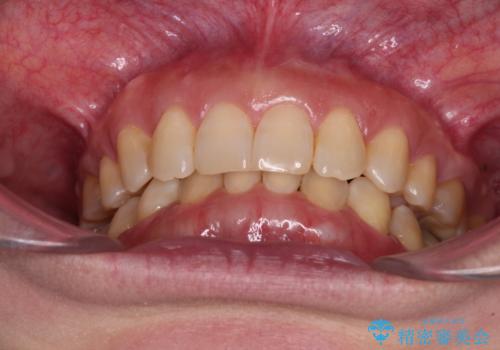

マウスピースでの抜歯矯正特有の抜歯スペースに向かって奥歯が傾斜する動きが顕著に表れ、ディープバイトは改善されませんでした。

前歯のみが強く接触し、奥歯で咬めない期間も続いたため、ワイヤー装置などを補助的に使用し、何とか終了させることができました。